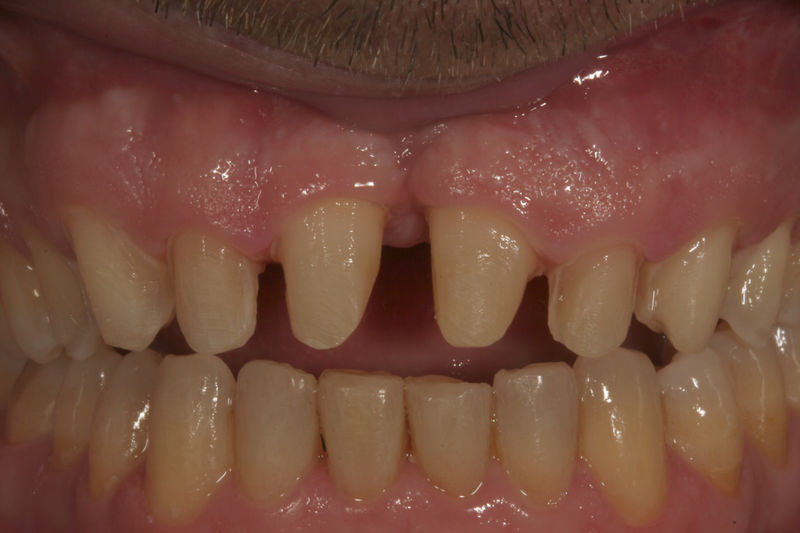

Las prótesis dentales son aparatos o dispositivos que se utilizan para reemplazar los dientes ausentes y las estructuras orales relacionadas.

Los implantes dentales son pequeños tornillos de titanio u otro material biocompatible que se insertan en el hueso maxilar o mandibular para sustituir la raíz de un diente perdido. Actuando como un soporte sólido sobre el cual el dentista puede colocar un diente artificial (corona), un puente o una prótesis completa.

Restauraciones fabricadas en el laboratorio con materiales estéticos, los cuales se usan para reemplazar dientes ausentes usando coronas como soporte. Para poder enviar el caso al laboratorio se toman impresiones utilizando materiales de impresión o técnicas modernas digitales.